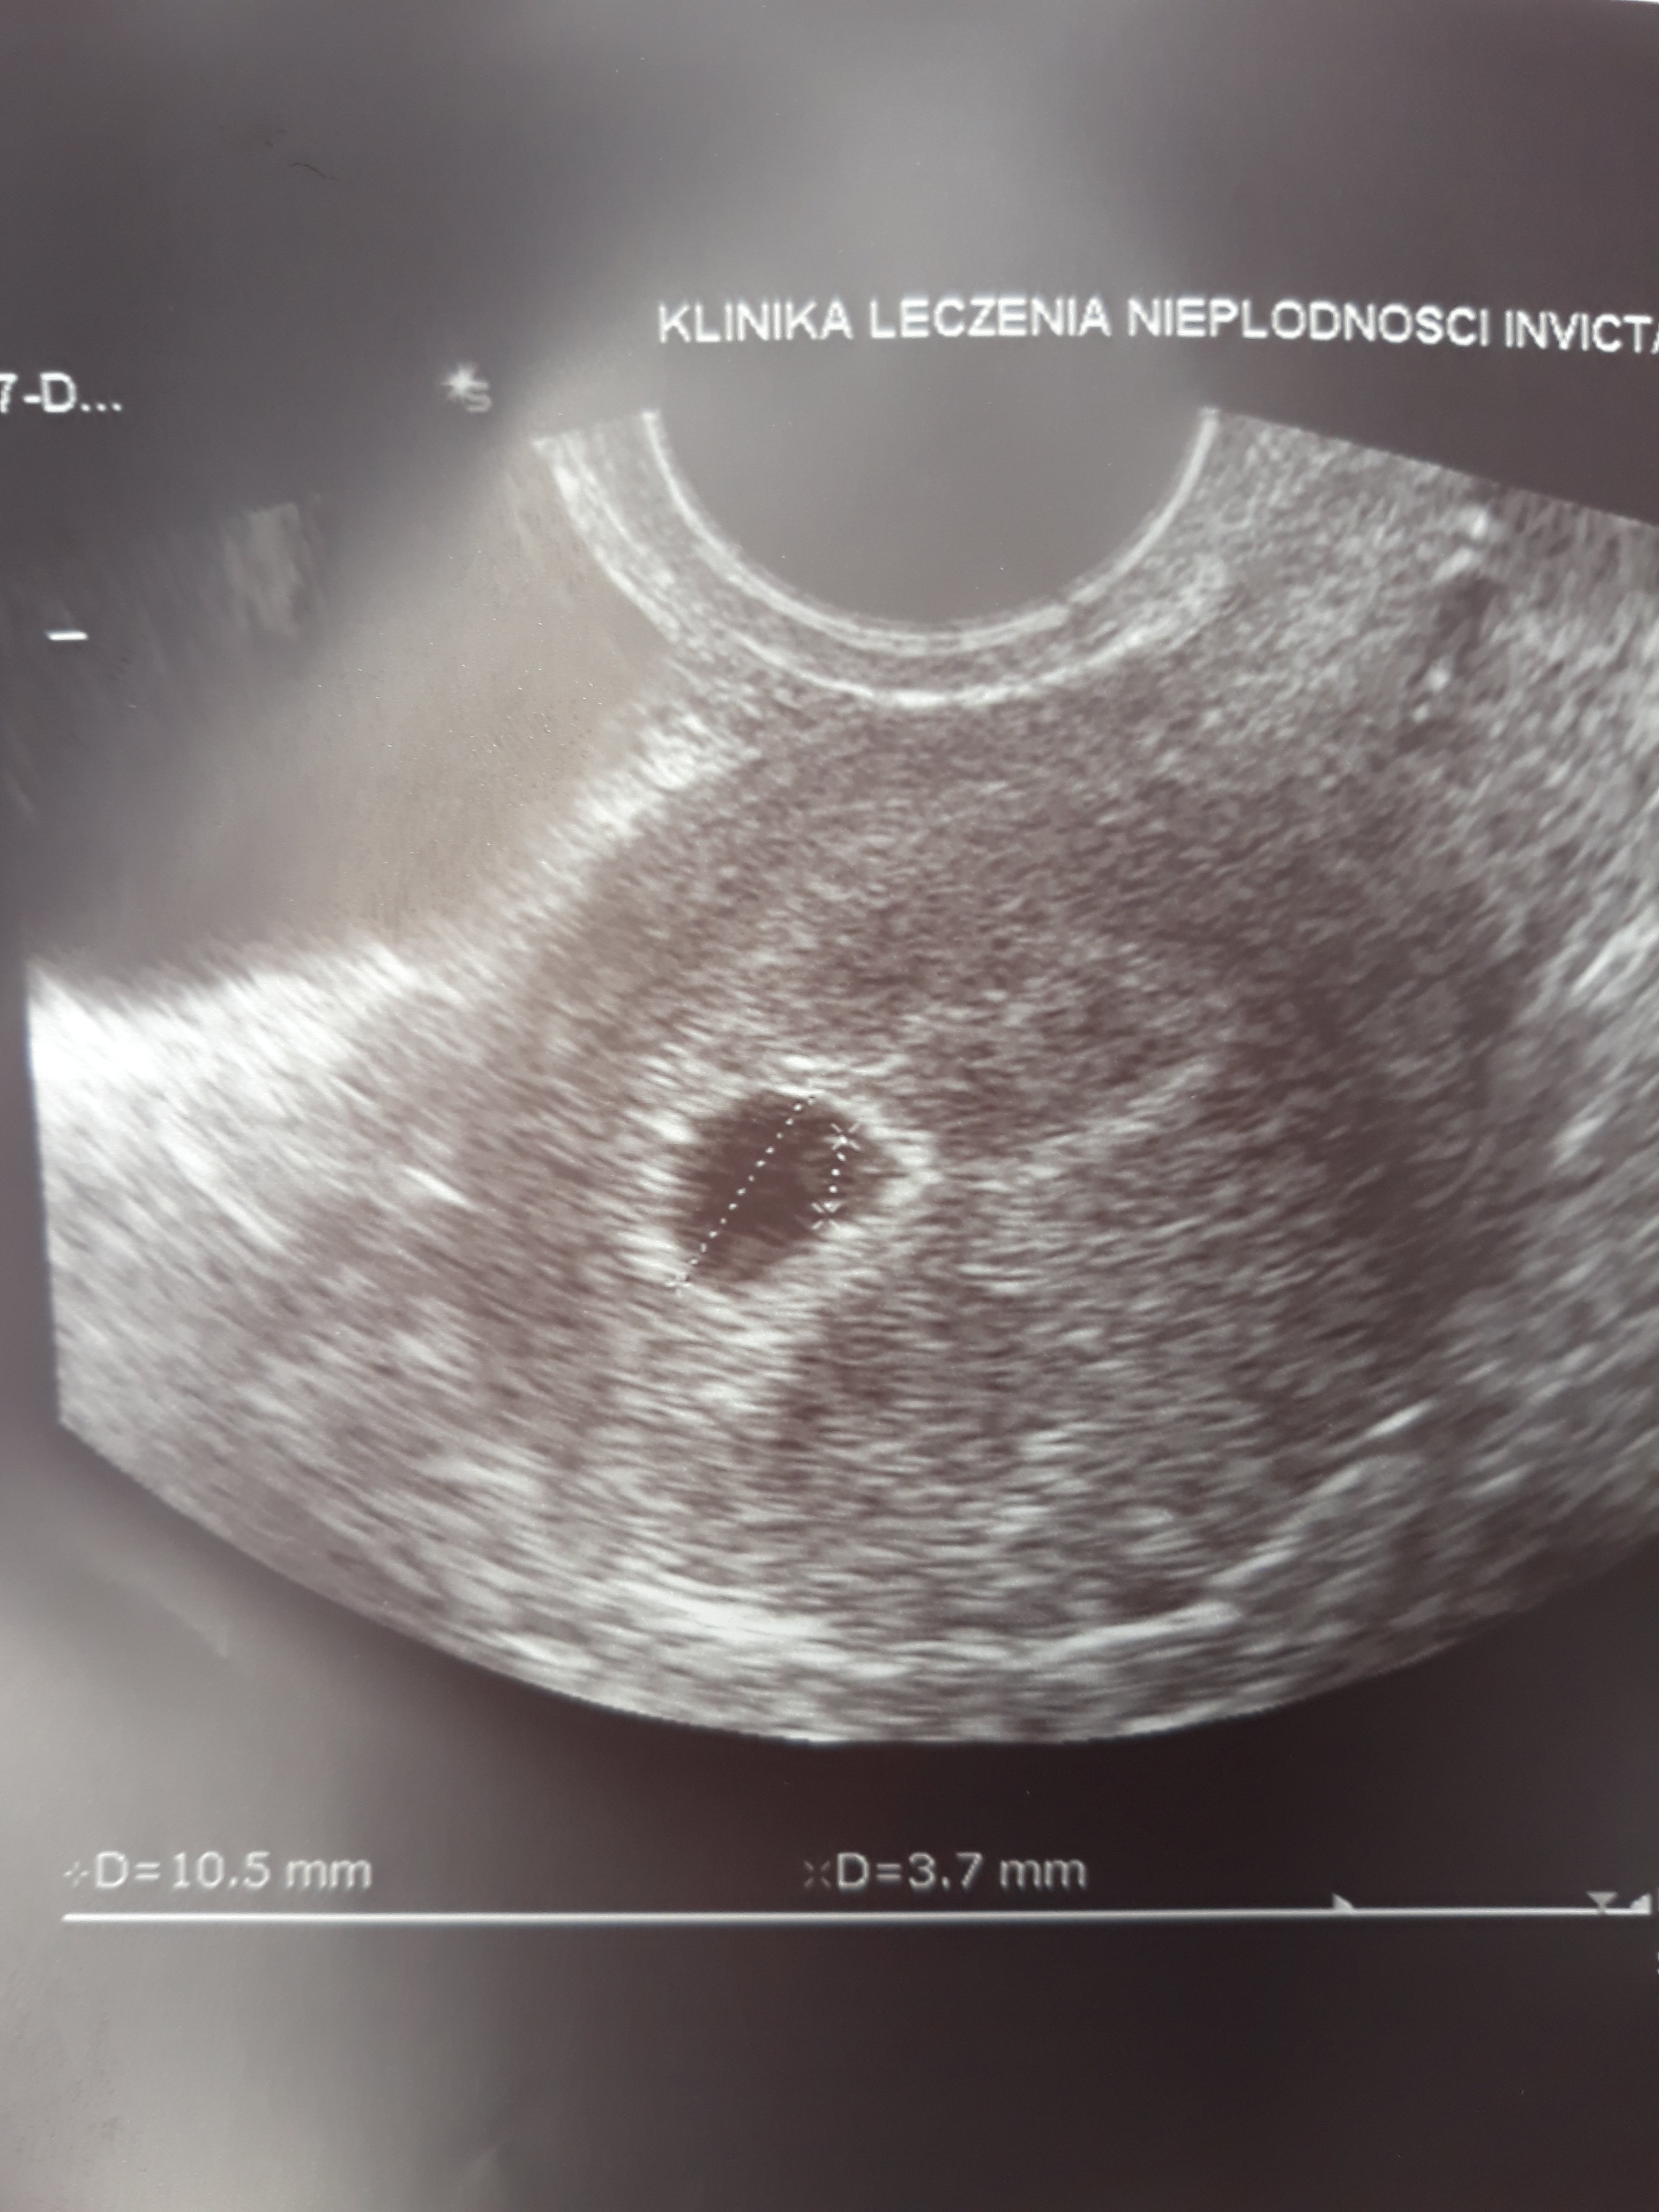

Kochane mamy jeden zarodeczek 10mm z cialkiem zoltkowym

20180616_132852.jpg

• 20180616_132852.jpg

985,8 KB · Wyświetleń: 593